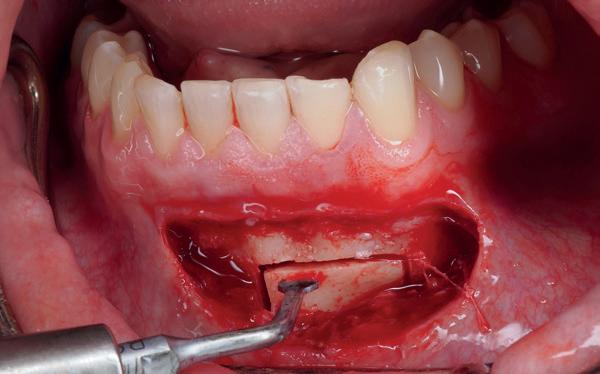

Implantologische behandelingen in het esthetische front vragen meer dan technische vaardigheid alleen. Ze vragen om overzicht, timing, vertrouwen en een team dat als vanzelf samenwerkt onder druk. Juist bij complexe casussen, waarin angst, infectie en hoge esthetische verwachtingen samenkomen, wordt zichtbaar hoe bepalend de rol van de tandartsassistent is.

Deze casus beschrijft een uitgebreide immediate implantaatbehandeling bij een patiënt die door meerdere collega’s werd geweigerd. Niet omdat de mogelijkheden ontbraken, maar omdat de complexiteit vroeg om een perfect afgestemde samenwerking. Het verhaal laat zien hoe de assistent in zo’n traject veel meer is dan een uitvoerende kracht of “mal”, maar een dynamische surgical guide die het proces mede stuurt, bewaakt en mogelijk maakt.De patiënt: wanneer alles samenkomt

Na het klinische onderzoek volgde het röntgenologisch traject. De CBCT liet precies zien wat we al vreesden: een front waarin het bot onregelmatig was, duidelijke radiolucenties rond de pijlers en een infectiegebied dat zich onder vrijwel de gehele brug had verspreid. Tegelijkertijd was er ook potentie. Net voldoende botstructuur om immediate implantaatplaatsing te overwegen, mits alles perfect gepland zou worden.